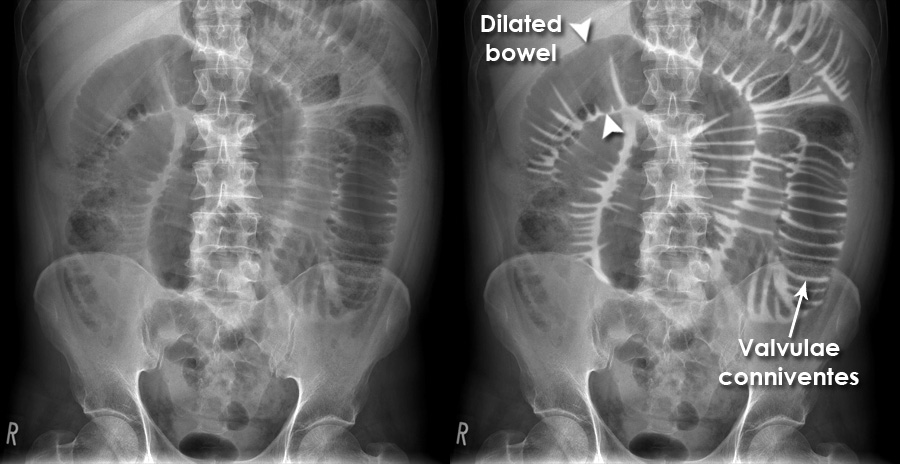

Diagnosis

- Imaging: X-ray (air-fluid levels), CT scan (site of obstruction).

| small bowel obstruction x ray |